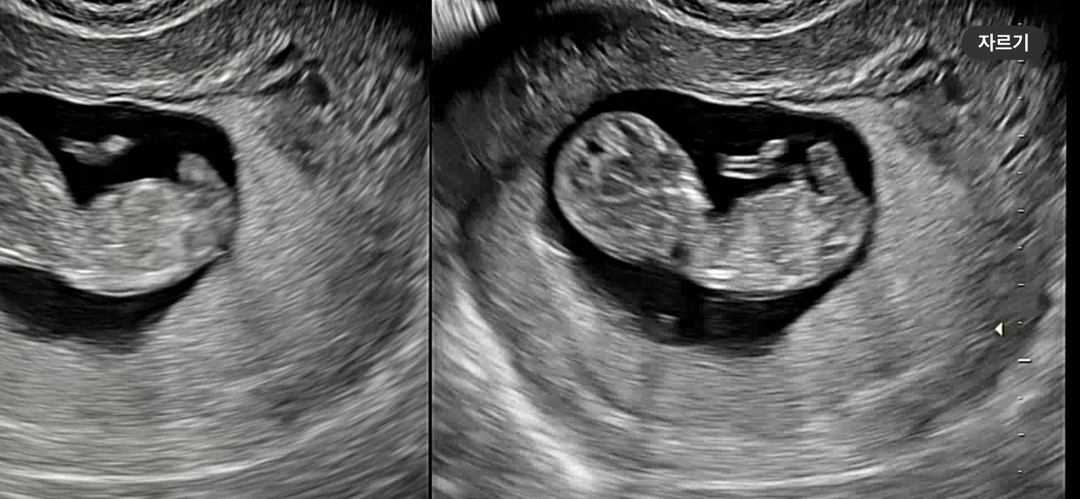

각도법..? 부탁드려요!!!

이 사진으로도 알 수 있을까요??ㅎㅎ